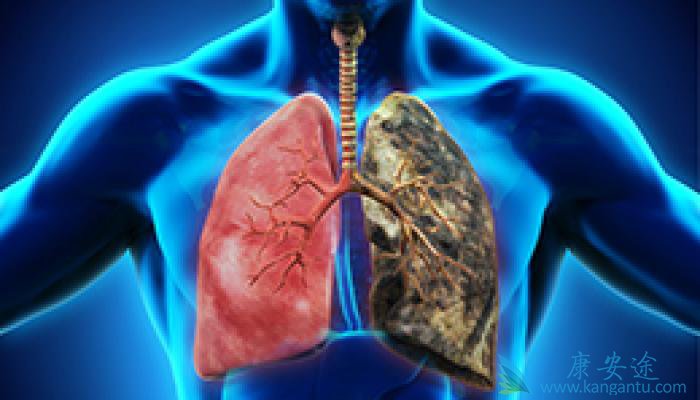

小细胞肺癌 预防的方法主要是通过日常的生活习惯和饮食安排,这是预防小细胞肺癌的根本。那么,生活习惯和饮食具体是如何预防小细胞肺癌的呢?快来一起了解了解吧。小细胞肺癌的预防方法第一是要控制和禁止吸烟,吸烟致肺癌的机理现在已经研究比较清楚 ...

肺癌是一种高度恶性的肿瘤,在我国肺癌的发病率和死亡率都相当高。人们一旦确诊是肺癌以后,无论是对患者本身还是患者的家人带来巨大影响,对癌症的恐惧会使肺癌患者的整个家庭都笼罩在恐惧和死亡的阴霾中。很多肺癌患者或其家属都很关心,到底得了肺癌 ...

肺癌是目前各种肿瘤中发病率和死亡率最高的肿瘤,被称为肿瘤第一杀手。当肺癌发生骨转移,就意味着肺癌已发展到最晚的一期,治疗效果比较差,所以发现肺癌后,应接受专业医师指导,积极恰当地治疗,避免病情进一步发展。 肺癌骨转移症状 有哪些?疼痛是 ...

提到发热,大家的第一反应,是不是感冒了,病毒感染或者细菌感染,其实肺癌组织坏死也是可以引起发热的,我们称之为癌性发热,另外肺癌常常导致阻塞性肺炎,这也是引起发热的一大重要原因,这个时候,使用抗生素往往效果不佳。除了发热 肺癌早期有什么症 ...